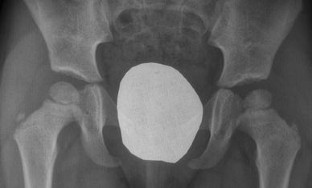

Inflammatory or septic arthritis due to Mp is an extremely unusual manifestation in children, and the functional outcome of the joints is difficult to be predicted. Two cases with Mp infection are presented. The first patient had positive PCR for Mp after hip aspiration and arthrotomy with thorough irrigation and debridement. A flattened femoral head was detected during the follow-up, which became quite spherical a year after. An arthrotomy with medial synovectomy of the knee was performed in the second patient. Lack of full knee extension was presented during the first 3 months, which gradually decreased to 7° in the final follow-up. The suspicion of Mp infection with extra-pulmonary involvement in children is mainly based on clinical, epidemiological and radiological data, but laboratory testing is required for confirmation. Rapid diagnosis of probability consists of serum tests, and their results are essential for early therapeutic planning. The direct diagnosis of Mp DNA through polymerase chain reaction (PCR) provides specificity and sensitivity. Very few cases of arthritis associated with Mp infection have been published but not with the severity of our cases. Clinical suspicion of Mp infection is of great importance, and the outcome depends on early diagnosis and specific treatment.

Fig. 4